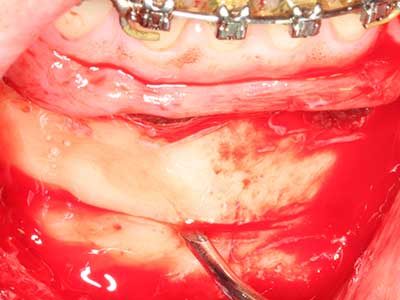

Indication: Periodontal therapy

Marginal periodontal diseases are the main reason for extractions in advanced age. These diseases are primarily caused by bacterial colonization of the gingival pocket, which causes inflammation followed by loss of the periodontium. The formation of subgingival biofilms and concrements is a significant aetiological factor for marginal bone atrophy, so their removal is an important part of the treatment (Drisko 2014, Plessas 2014).

Initial and surgical treatment phases are differentiated in the treatment of marginal periodontitis. In addition to instruction in oral hygiene and motivating patients, both phases should include adequate cleaning of the root surface. In the regenerative setting an open access is generally preferred. The root surface can be cleaned by piezo surgery using special attachments, where instruments with different curvatures are used to reach areas that are difficult to access, such as furcations. The integrated irrigation in the system flushes the detached concrements and bacteria out of the pocket. Specialized systems such as the Piezomed also include application feedback to minimize the ablation of hard dental substance. The greater the pressure on the periodontal attachment the greater the reduction in the amount of ablation.